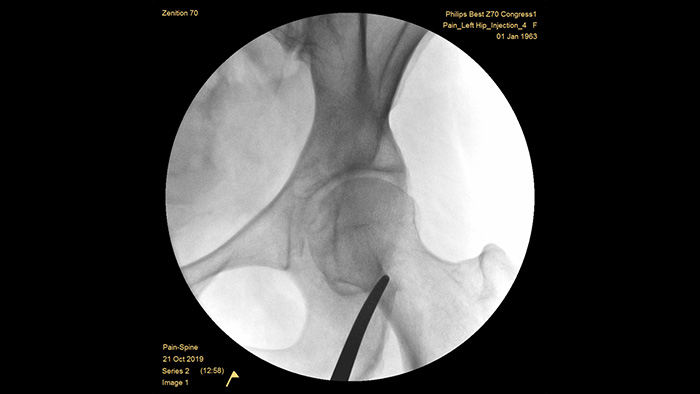

A Philips construiu uma reputação de excelência em diagnóstico por imagem e eficiência de dose ao longo de mais de meio século de experiência no desenvolvimento de sistemas de arcos cirúrgicos portáteis para cenários cirúrgicos. Nossas soluções de cirurgia portáteis Zenition, desenvolvidas com uma abordagem abrangente do gerenciamento de doses, proporcionam qualidade de imagem clinicamente relevante durante procedimentos intervencionistas para aplicações de manejo da dor. Além disso, gerenciam com eficiência a exposição à radiação de pacientes e da equipe médica.

A profundidade otimizada do arco cirúrgico totalmente contrabalançado fornece um amplo espaço de posicionamento em torno de pacientes obesos e captam a imagem da coluna lombar e quadril. O dispositivo favorece o posicionamento sobre a mesa, mesmo no caso de mesas com uma base grande.